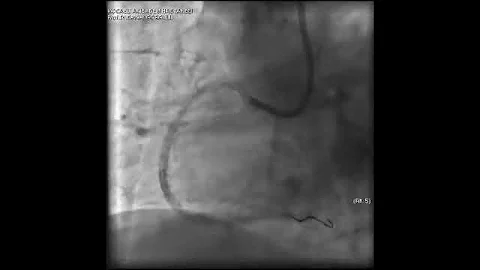

Complex Pci For Rca Cto With Bifurcation At Distal Cap Video 7